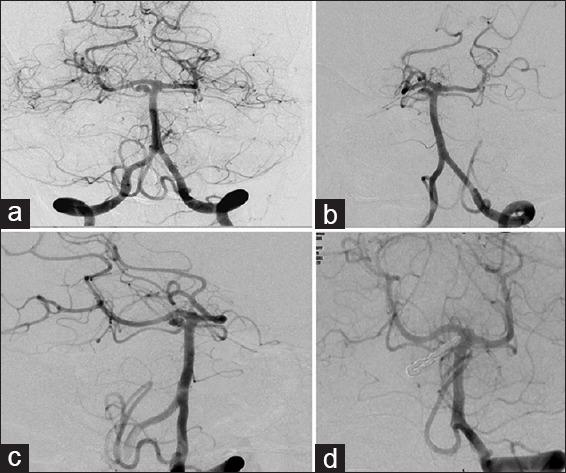

All patients with SCA were evaluated with computerized tomography angiography and/or digital subtraction angiography (DSA) prior to surgery. All patients in our series underwent microsurgical clipping and postoperative DSA to assess the extent of aneurysm occlusion. The Glasgow outcome scale (GOS) and the modified Rankin's scale (mRS) were used to grade their postoperative neurological status at discharge and 6 months, respectively.

Fourteen patients had SCA aneurysms (ruptured-9, unruptured-5). There were 10 females and 4 males with the mean age of 47.2 years (median - 46 years, range = 24-66 years). Subarachnoid hemorrhage (SAH) was seen in 11 patients. The mean duration of symptoms was 2.5 days (range = 1-7 days). The WFNS score at presentation was as follows: Grade 1 in 10 cases, II in 2 cases, III in 1 case and IV in 1 case. In the 9 cases with ruptured SCA aneurysm, average size of the ruptured aneurysms was 7.3 mm (range = 2.5-27 mm, median = 4.9 mm). The subtemporal approach was used in the first 7 cases. The extradural temporopolar (EDTP) approach was used in the last 5 cases. Complications include vasospasm (n = 6), third nerve palsy (n = 5) and hydrocephalus (n = 3). Two patients died following surgery. At mean follow-up 33.8 months (median - 25 months, range = 19-96 months), no patient had a rebleed. At discharge 9 (64%), had a GOS of 4 or 5 and 3 (21%) had a GOS of 3. At 6 months follow-up, 10/14 (71%) patients had mRS of 0-2, and 2 (14%) had mRS of 5.

14例患者患有SCA动脉瘤(破裂9例,未破裂5例)。有10名女性和4名男性,平均年龄为47.2岁(中位数 - 46岁,范围 = 24 - 66岁)。11例患者出现蛛网膜下腔出血(SAH)。症状的平均持续时间为2.5天(范围 = 1 - 7天)。就诊时的WFNS评分如下:1级10例,II级2例,III级1例,IV级1例。在9例破裂的SCA动脉瘤中,破裂动脉瘤的平均大小为7.3 mm(范围 = 2.5 - 27 mm,中位数 = 4.9 mm)。前7例采用颞下入路。后5例采用硬膜外颞极(EDTP)入路。并发症包括血管痉挛(n = 6)、动眼神经麻痹(n = 5)和脑积水(n = 3)。2例患者术后死亡。平均随访33.8个月(中位数 - 25个月,范围 = 19 - 96个月),无患者再次出血。出院时,9例(64%)患者的GOS为4或5,3例(21%)患者的GOS为3。在6个月随访时,14例患者中有10例(71%)的mRS为0 - 2,2例(14%)的mRS为5。